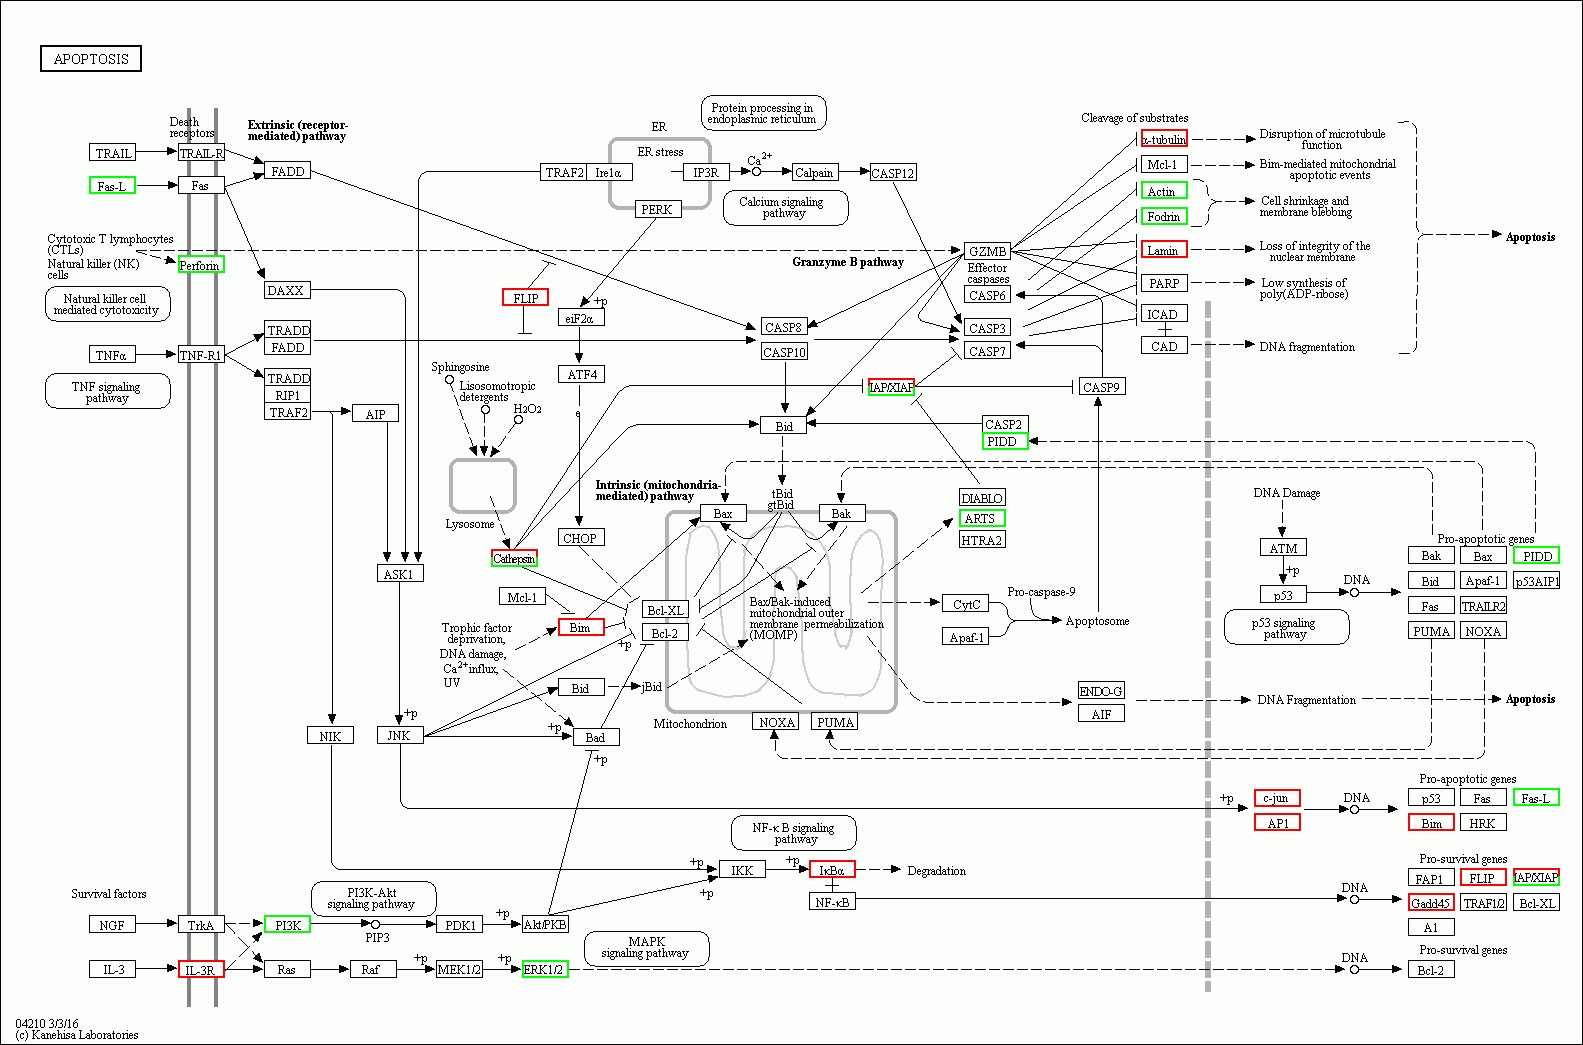

2 结果48 h各组病理结果,对照组脾组织结构正常(见图 1A )。脓毒症组脾组织见白髓结构破坏,红白髓交界模糊,多量组织细胞浸润,红髓充血(见图 1B)。差异mRNA的Volcano-plot分布图(见图 2)。相比于对照组,24 h时脓毒症组脾组织mRNA表达上调的有1 030个,下调的有935个[5];48 h组表达上调的有1 354个,下调的有1 763个。差异mRNA的聚类情况(见图 3)。GO功能分类结果(见图 4)。脓毒症大鼠脾组织部分通路相关基因表达情况(见图 5、6):脓毒症大鼠24 h,48 h脾组织关于细胞因子及其受体相互作用通路相关基因的分布图(见图 7,图 8)。脓毒症大鼠24 h,48 h脾组织关于细胞凋亡相关通路的基因分布图(见图 9,图 10)。

| 图 9 脓毒症大鼠24 h组 |

| 图 10 脓毒症大鼠48 h组 |

(2)脓毒症晚期脾组织相关细胞的凋亡系脓毒症晚期脾功能障碍的原因之一。从图 9-10可以看出,在细胞凋亡相关通路中,脓毒症大鼠24 h脾组织mRNA表达上调,48 h表达下调有1个:Gadd45。24 h表达上调,而48 h正常表达的基因有5个:IL-3R、IκBα、a-tubulin、c-jun、AP1。24 h正常表达,而48 h转为表达下调的基因有9个:TRAIL、NGF、TRAF2、NIK、Cathepsin、GZMB、ICAD、Apaf-1、TRAF1/2。24 h正常表达,而48h转为表达上调的基因有10个:Ras、PDK1、Irelα、eiF2α、IKK、CASP6、DLABLO、CytC、PARP、NOXA。脓毒症大鼠24 h脾组织mRNA表达下调,而48 h转为表达上调的基因有1个:Actin。24 h表达下调转为正常表达的有1个:fas-L。脓毒症晚期大鼠脾组织细胞凋亡相关通路中的基因表达紊乱,可能是晚期脾功能障碍的原因之一,特别是胞膜空泡化相关基因Actin从下调转为上调,促凋亡相关基因NOXA从正常表达转为上调,促生存基因Gadd45从表达上调转为下调,促生存基因TRAF1/2从正常表达转为下调直接促进相关细胞的凋亡。